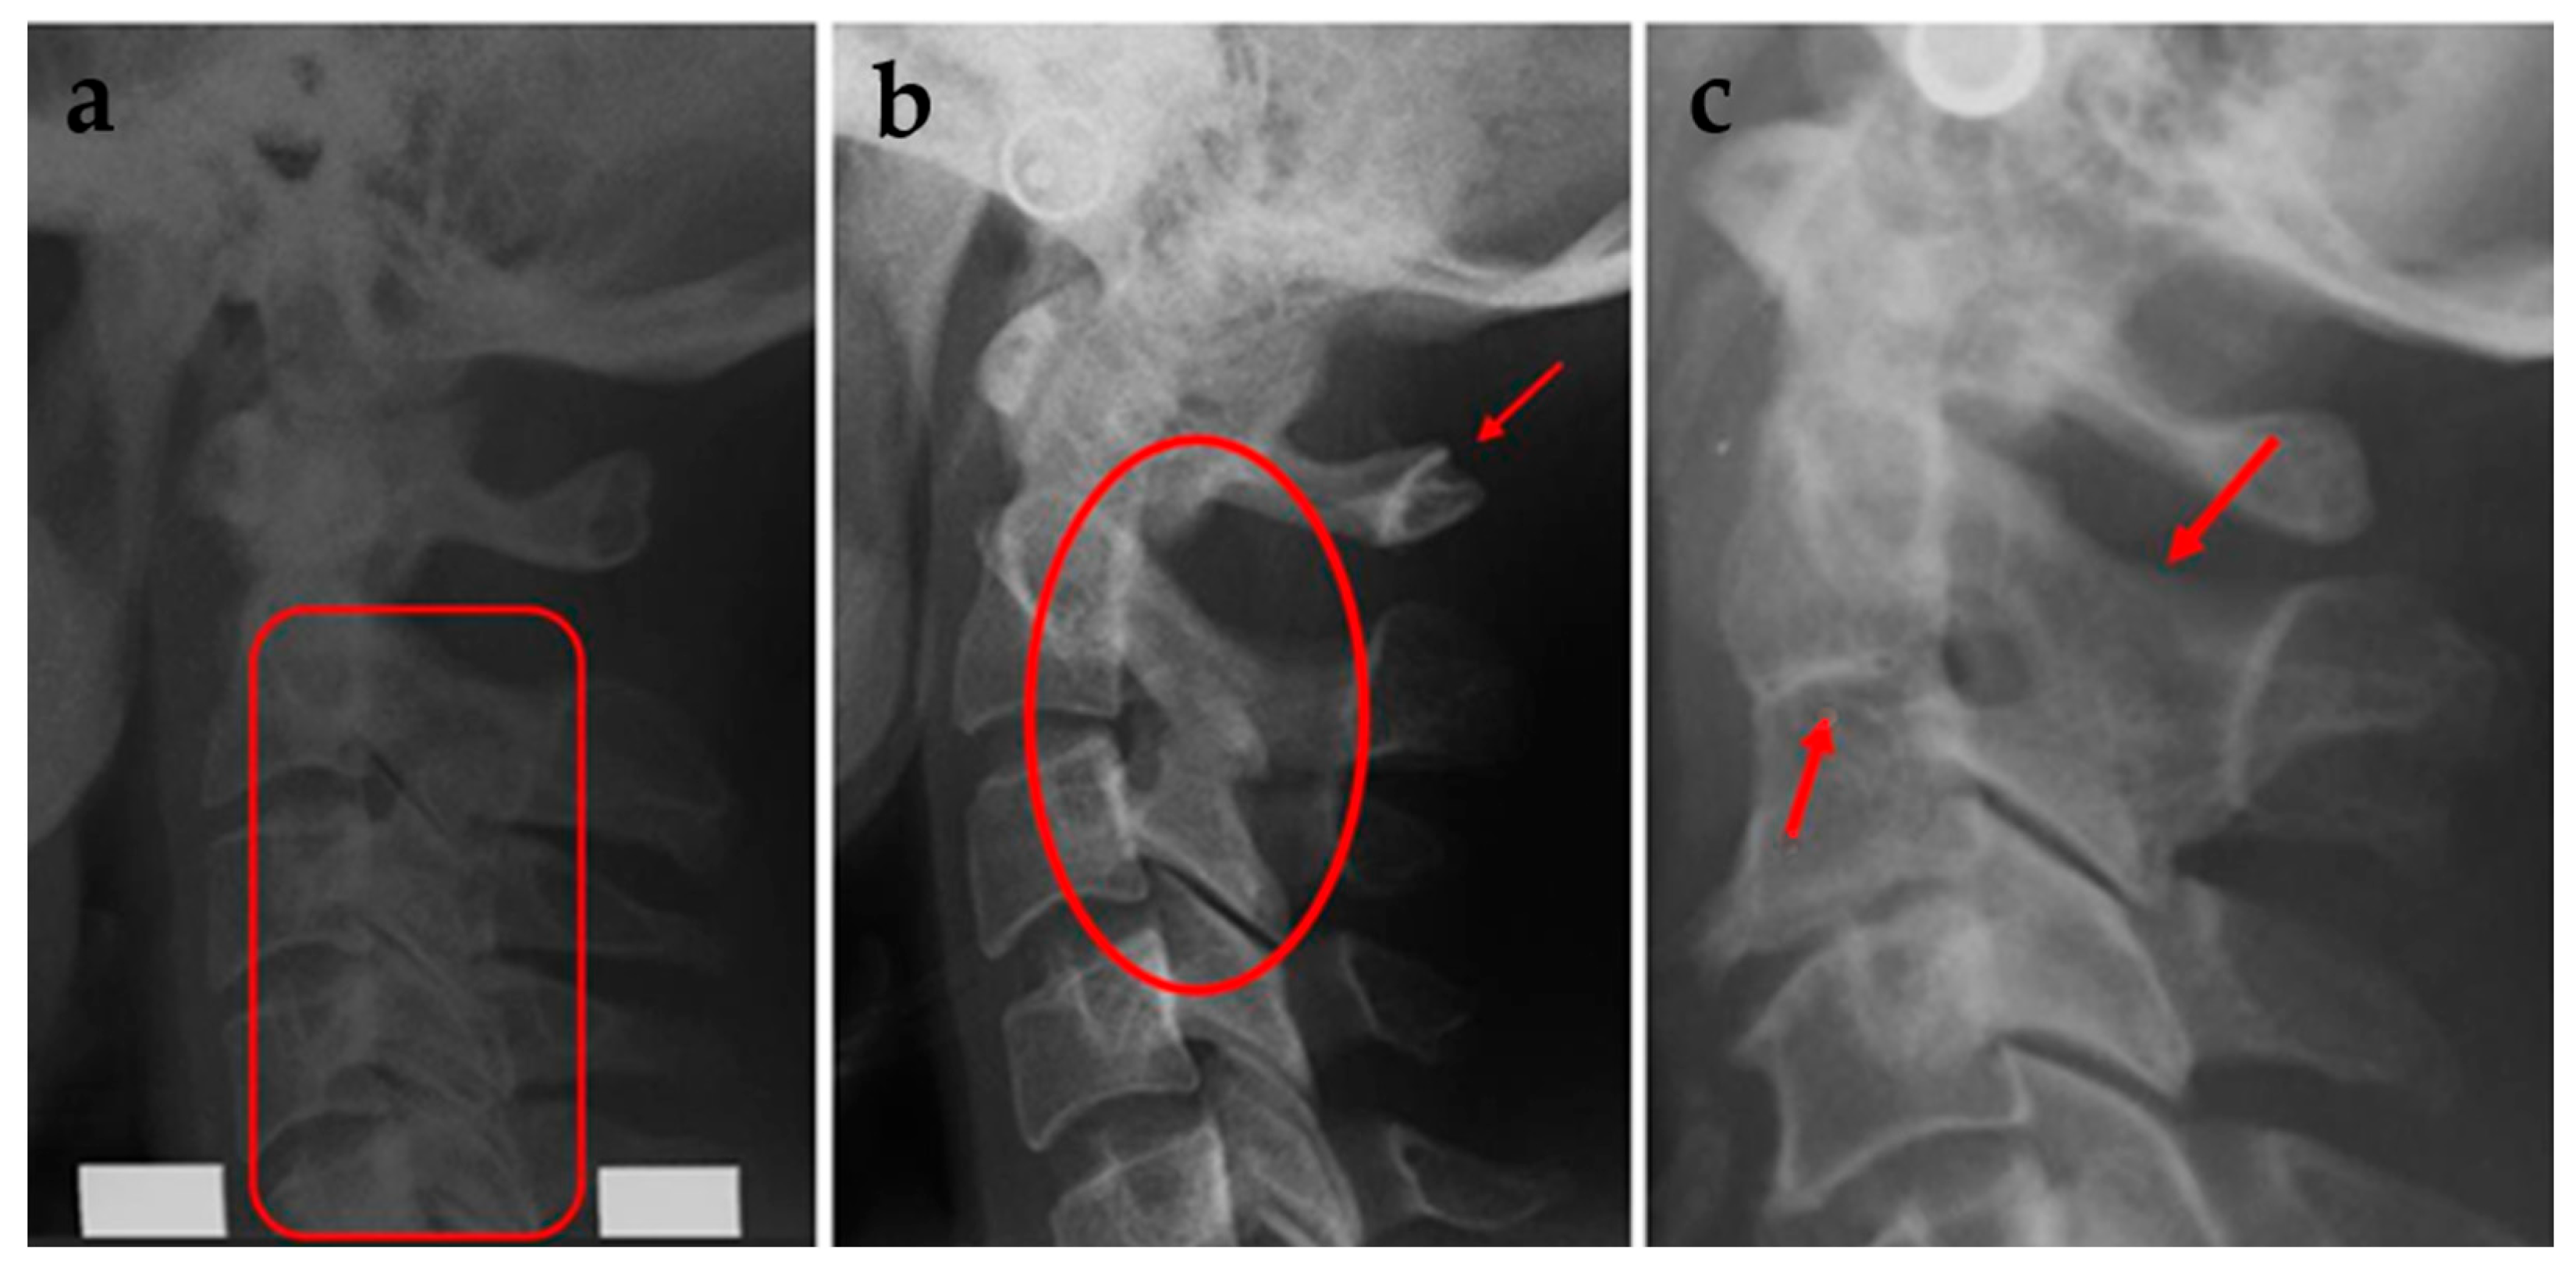

| Fusion (C2-C3 or C4-C5) | 16 | 31.4% | 12 | 16.2% | 0.117 |

| Block fusion | 5 | 9.8% | 0 | 0 | 0.465 |

| Total number of fusion anomalies | 21 | 41.2% | 12 | 16.2% | 0.05 **ab |

| Posterior arch deficiency (PAD) | |||||

| Partial cleft | 8 | 15.7% | 10 | 1f3.5% | 0.614 |

| Dehiscence | 2 | 3.9% | 0 | 0 | 0.991 |

| Total number of PADs | 10 | 19.6% | 10 | 13.5% | 0.758 |

| More than 1 deviation | 6 | 11.8% | 2 | 2.7% | 0.341 |

| Total upper spine deviations | 25 | 49% | 20 | 27% | 0.271 |